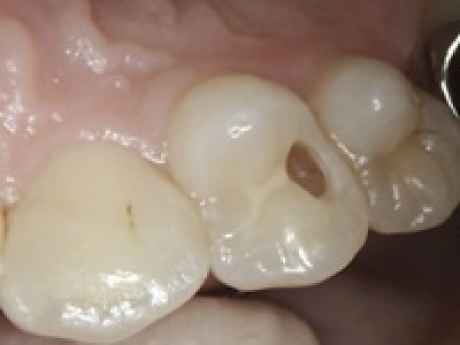

case2